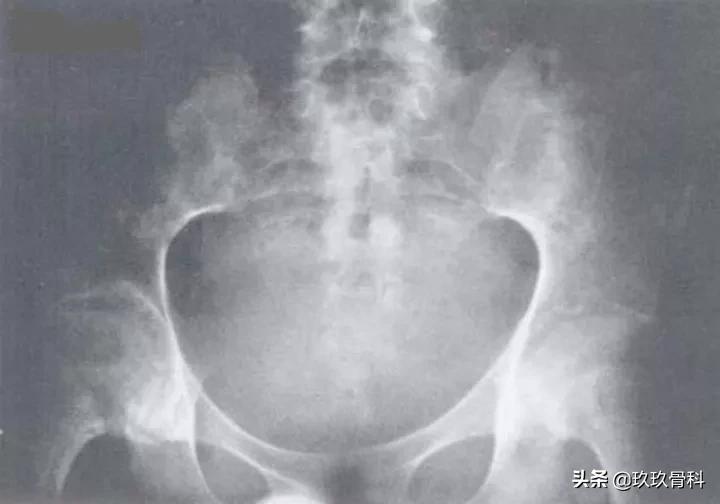

强直性脊柱炎(Ⅳ级)

图注:双侧骶髂关节骨质破坏,关节间隙消失,骨性强直。双侧髋关节面侵蚀,轮廓粗糙不光滑,以髋臼明显,骨盆疏松。